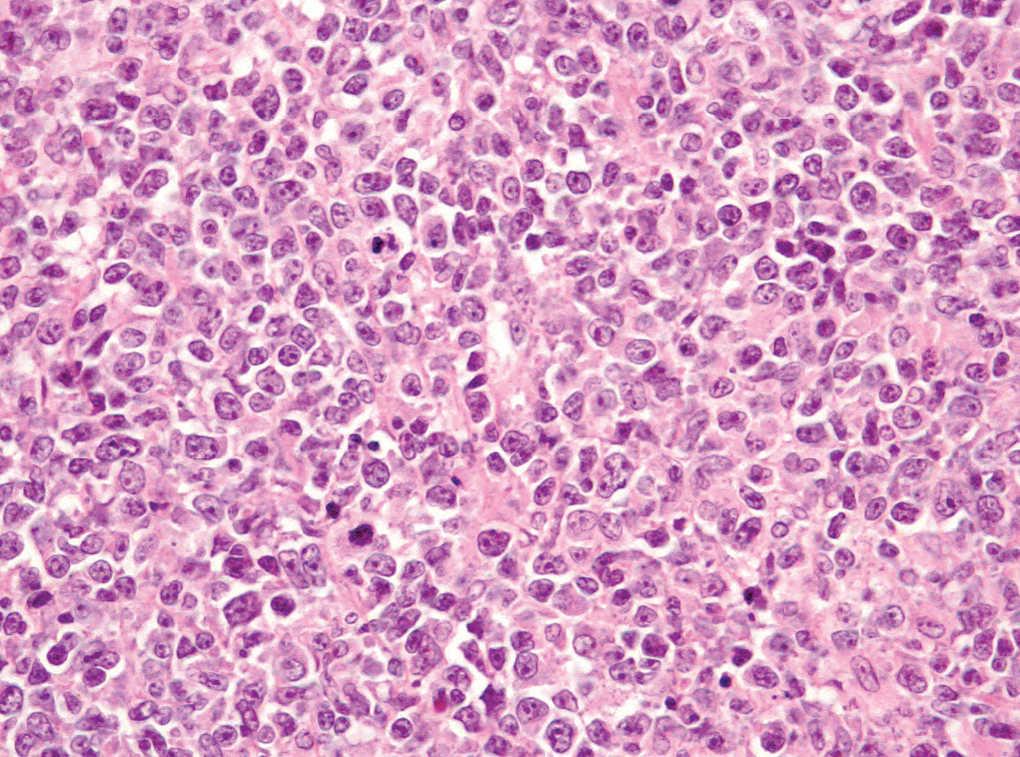

Dentro del infiltrado, densamente celular, predominaban los linfocitos de tamaño grande con núcleos redondeados, nucléolo excéntrico y cromatina finamente dispersa, que recordaban a los centroblastos; entre ellas se observaban frecuentes figuras de mitosis (fig. 3), así como una población de células de menor tamaño con núcleos más hipercromáticos y contornos más irregulares que corresponderían también a linfocitos aunque su número era menor (fig. 4). Se realizó tinción para CD20 que resultó intensamente positiva en la membrana de las células tumorales. El infiltrado resultó positivo para CD10 y bcl-2, y negativo para CD30 y bcl-6 (figs. 5 y 6).

Fig. 3.--Infiltrado densamente celular en el que predominan los linfocitos de tamaño grande que recuerdan a los centroblastos; entre ellas que se objetivan frecuentes figuras de mitosis. (Hematoxilina-eosina, x200.)

Fig. 4.--Detalle del infiltrado formado principalmente por células grandes de núcleos redondeados y nucléolo excéntrico que recuerdan a centroblastos. Se observan abundantes figuras de mitosis (Hematoxilina-eosina, x400.)